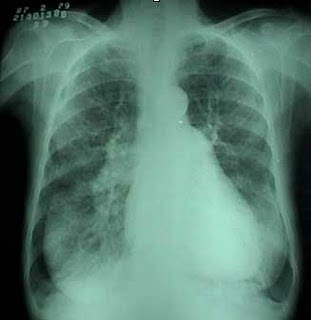

LUNG CANCER DISEASE